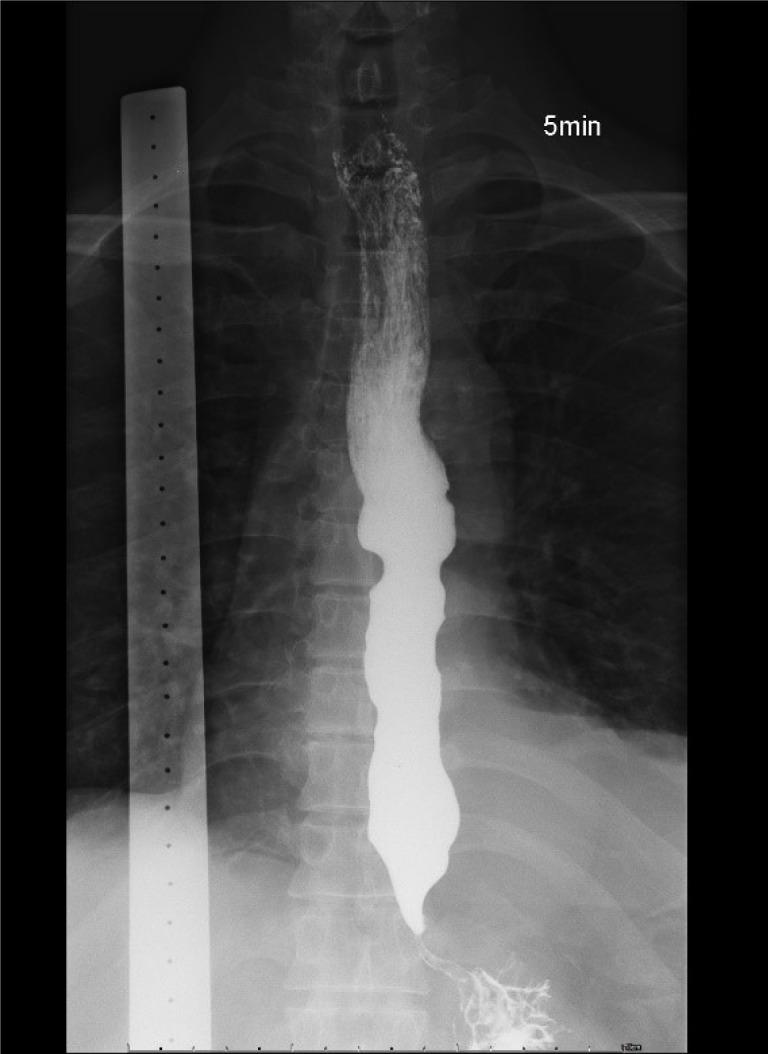

We report the case of a 60-year-old man who presented with progressive dysphagia, weight loss, and nocturnal cough. Esophagogastroduodenoscopy, timed barium esophagogram, and high-resolution manometry were conducted. The results of these investigations supported a diagnosis of type II idiopathic achalasia. However, preoperative computed tomography revealed atypical findings, which prompted further evaluation. Repeat endoscopy with magnifying narrow-band imaging identified abnormal mucosal and vascular patterns, and endoscopic ultrasound demonstrated hypoechoic submucosal lesions with involvement of the muscularis propria. Targeted biopsies confirmed moderately differentiated ESCC. Positron emission tomography revealed extensive metastatic disease; therefore, the patient was diagnosed with stage IVB ESCC. Peroral endoscopic myotomy was aborted, and the patient was referred for palliative chemoradiotherapy.

我们报告了一名60岁男性的病例,该患者表现为进行性吞咽困难、体重减轻和夜间咳嗽。进行了食管胃十二指肠镜检查、定时食管钡餐造影和高分辨率测压法。这些检查结果支持II型特发性贲门失弛缓症的诊断。然而,术前计算机断层扫描显示出非典型表现,这促使进一步评估。重复内镜检查并使用放大窄带成像识别出异常的黏膜和血管模式,内镜超声显示低回声黏膜下病变累及固有肌层。靶向活检确诊为中分化ESCC。正电子发射断层扫描显示广泛转移;因此,该患者被诊断为IVB期ESCC。经口内镜下肌切开术中止,患者被转诊接受姑息性放化疗。